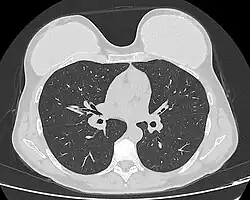

Computed tomography of a woman with breast implants

Chest X-ray showing breast implants